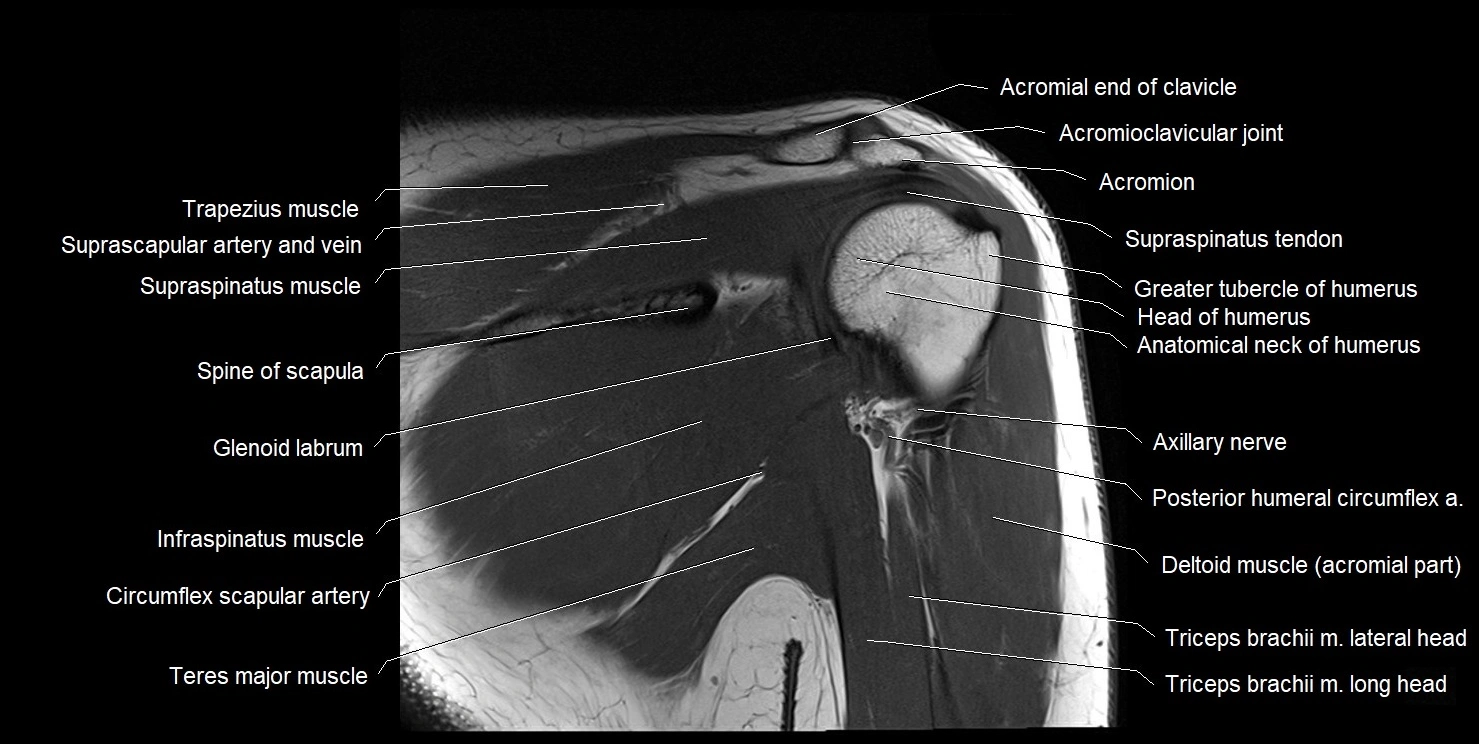

The acromial end of the clavicle is the flattened lateral extremity of the clavicle that articulates with the acromion of the scapula to form the acromioclavicular (AC) joint. Unlike the sternal end, the acromial end is broad and compressed. Its articular surface is oval, directed downward and medially, and covered with fibrocartilage.

The AC joint is stabilized by the acromioclavicular ligaments (superior and inferior) and reinforced by the coracoclavicular ligaments (conoid and trapezoid), which prevent vertical displacement. Small intra-articular fibrocartilaginous discs may be present.

This region is highly mobile, allowing scapular rotation, gliding, and elevation, which are essential for full shoulder motion. It is clinically significant as a frequent site of degeneration, separation injuries, fractures, and osteoarthritis.

MRI Appearance

T1-weighted images:

• Bone marrow: intermediate signal

• Cortical bone: hypointense rim

• AC joint space: visible as a thin hypointense line

T2-weighted images:

• Cartilage: hyperintense

• Joint fluid or effusion: bright signal

• Detects degenerative changes and joint inflammation

PD-FS (Proton Density Fat-Suppressed):

• Enhances visualization of capsule, ligaments, and marrow edema

• AC joint pathology (arthritis, capsular injury, synovitis) appears hyperintense

• Excellent for trauma and subtle instability assessment